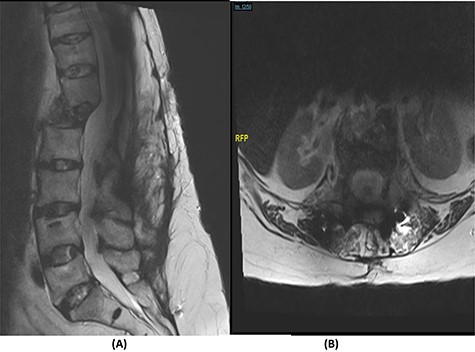

Radiological and laboratory investigations for possible malignancy or infection were done, and results were negative for malignancy. Erythrocyte sedimentation rate (ESR) was 50 mm/h and C-reactive protein (CRP) level was 38 mg/l. A magnetic resonance imaging (MRI) scan of the spine with contrast showed a significant pathological fracture of L1 along with spinal cord compression (Fig. 1). The patient underwent posterior spinal decompression of T12–L1 and pedicle instrumentation of T11–L3 with tissue and bone biopsy.

(A) T2-weighted sagittal lumbar spine MRI demonstrating a pathological fracture of L1 with spinal canal and neural foramina stenosis and cord edema and epidural and prevertebral soft tissue components. (B) T2-weighted axial lumbar spine MRI of the corresponding level of L1 vertebral body.